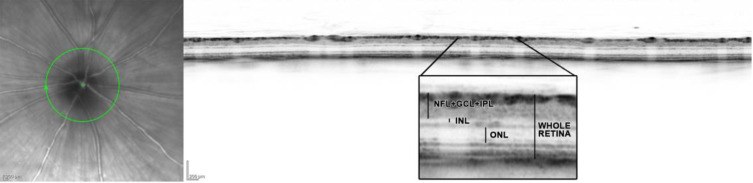

Methods: In this study, we used Cliff test to assess stereoscopic vision and spectral domain optical coherence tomography (SD-OCT) to evaluate retinal changes in an in vivo model of visual deprivation treated with Transcranial Direct Current Stimulation (tDCS).

Results: The depth perception test initially revealed differences between individuals with amblyopia and the control group. However, after 8 tDCS sessions, amblyopic subjects matched the control group's performance, which remained stable Additionally, significant changes were observed in retinal structures post-tDCS treatment. Specifically, the thickness of the Nerve Fiber Layer + Ganglion Cell Layer + Inner Plexiform Layer (NFL+GCL+IPL) increased significantly in amblyopic eyes (p<0.001). Moreover, significant retinal thickening, including the Nerve Fiber Layer + Ganglion Cell Layer + Inner Plexiform Layer (NFL+GCL+IPL) and the entire retina, was observed post-tDCS treatment (p<0.05), highlighting the critical role of tDCS in ameliorating amblyopia. Additionally, treated animals exhibited reduced thickness in the Inner Nuclear Layer (INL) and Outer Nuclear Layer (ONL).